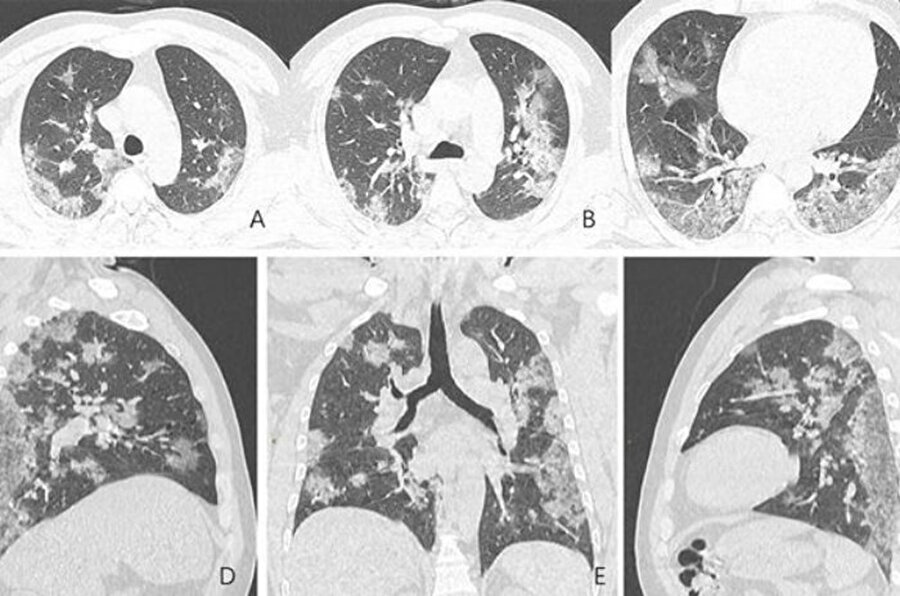

Çin'in Hubey eyaletine bağlı Wuhan'daki salgının kaynağı olduğu düşünülen hayvan pazarında çalışan 44 yaşındaki bir Çinlinin röntgen filmleri yeni tip corona virüsün akciğerlere verdiği zararı açıkça gösteriyor. Filmlerde akciğerdeki hava boşluklarının çoğunluğunun virüs nedeniyle dolduğu görülüyor. Uzmanlar, taramalarda görülen beyaz lekelerin SARS ve MERS'te de mevcut olduğunu belirtti.

Kuzey Amerika Radyoloji Derneği (RSNA), yeni tip corona virüsün (Covid-19) ortaya çıktığı Çin’in Wuhan kentindeki salgının kaynağı olduğu düşünülen deniz ürünleri pazarında çalışan ve 44 yaşında virüs nedeniyle hayatını kaybeden bir adamın röntgen filmlerini kamuoyuyla paylaştı. Filmlerde corona virüsün akciğerleri nasıl tahrip ettiği net bir şekilde görülüyor.

Hava kesecikleri doluyor X-ray ışını taramalarında corona virüsün etkileği yerler beyaz olarak görülüyor. Uzmanlar, hastada virüsün akciğerlerdeki hava keseciklerini kısmen doldurduğunu ve akciğer nodüllerine sebep olduğunu belirtti. .Diğer taraftan aynı tip anormalliklerin SARS (Şiddetli Akut Solunum Sendromu) ve MERS (Ortadoğu Solunum Sendromu) vakalarında da görüldüğünü söylediler.

Röntgenleri paylaşılan adamın yaklaşık iki hafta boyunca ateş ve öksürük belirtileri göstermesinin ardından 25 Aralık 2019'da hastaneye kaldırıldığı bir hafta sonra ise hayatını kaybettiği açıklandı.